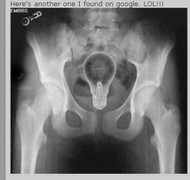

Bé trai 8 tuổi ở Quảng Nam phải nhập viện cấp cứu ngay khi nuốt đồng xu chơi game ở siêu thị.